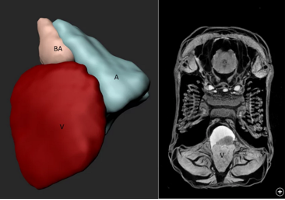

Imaging Platform

The central imaging core facility at the MPI for heart and lung research, provides a wide range of services and trainings, project specific support and full services for more than 100 scientists at the institute as well as for their collaboration partners. We also offer training for image analysis, develop custom analysis pipelines and help with data storage and archiving.